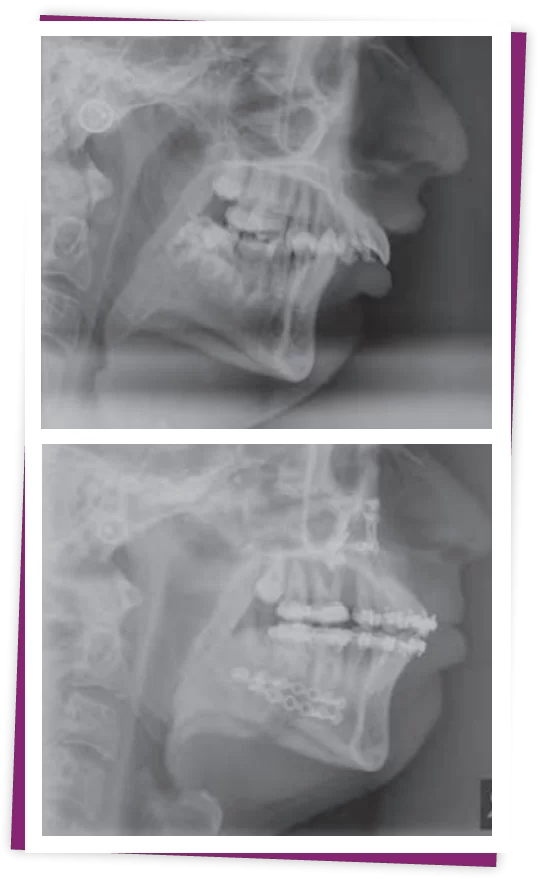

Bước 2: Tiến hành chụp CT scan từ đó xác định nguyên nhân, đánh giá và đề ra các phương pháp điều trị phù hợp nhất cho khách hàng

Để xác định chính xác tình trạng hàm hô, các bác sĩ sẽ tiến hành chụp phim CT 3D toàn hàm, kết hợp với các thao tác chuyên sâu để nắm rõ tỷ lệ hô, từ những thông số có được, bác sĩ sẽ đưa ra phương pháp điều chỉnh hàm hô phù hợp.